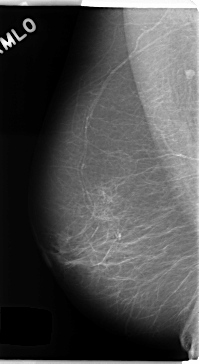

C_0188_1.LEFT_MLO

LEFT_MLO LINES 4728 PIXELS_PER_LINE 2552 BITS_PER_PIXEL 12 RESOLUTION 50 OVERLAY